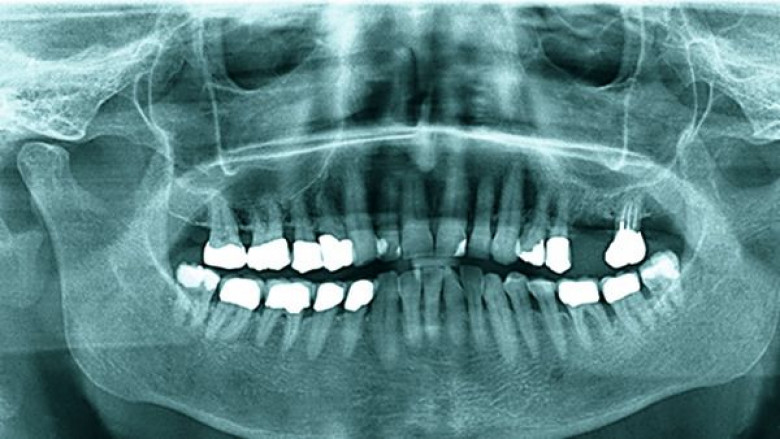

LifestyleՀամբուրգի 65-ամյա բնակչուհին դիմեց բժիշկներին՝ ասելով, որ չի կարողանում գտնել ատամները լվանալու ժամանակ կորցրած էլեկտրական խոզանակի կտորը: Բժիշկները նախ հետազոտեցին կնոջ ստամոքսն ու աղիները, բայց ոչինչ չհայտնաբերեցին և նրան ուղարկեցին տուն: Բայց մի քանի օր անց կինը կրկին դիմեց հիվանդանոց՝ գանգատվելով, որ ոչինչ չի կարողանում ուտել: Դիմածնոտային վիրաբույժը կնոջ բերանի խոռոչի փափուկ հյուսվածքներում 6 սմ երկարությամբ օտար առարկա նկատեց: Պարզվեց, որ դա հենց ատամի խոզանակի ջարդված կտորն էր: Վիրահատությունից հետո մի քանի օր անց կինը դուրս գրվեց: